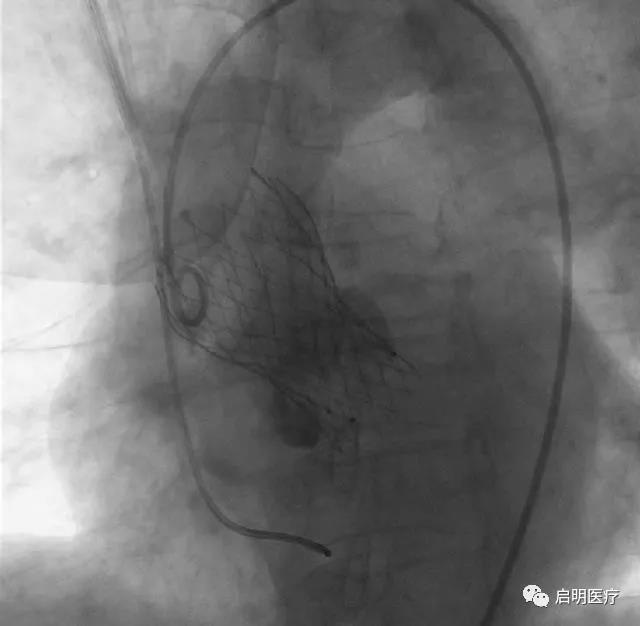

患者,76歲女性,診斷為:主動(dòng)脈瓣重度狹窄,外科手術(shù)高危(STS 13.8%)。經(jīng)浙醫(yī)二院心臟團(tuán)隊(duì)討論,該患者的解剖結(jié)構(gòu)特點(diǎn)為二葉式主動(dòng)脈瓣畸形、鈣化不對(duì)稱,瓣膜植入過(guò)程中移位的可能性大,手術(shù)難度高,適用于可回收系統(tǒng)。

浙醫(yī)二院王建安教授中國(guó)首例可回收經(jīng)導(dǎo)管主動(dòng)脈瓣膜

臨床應(yīng)用成功